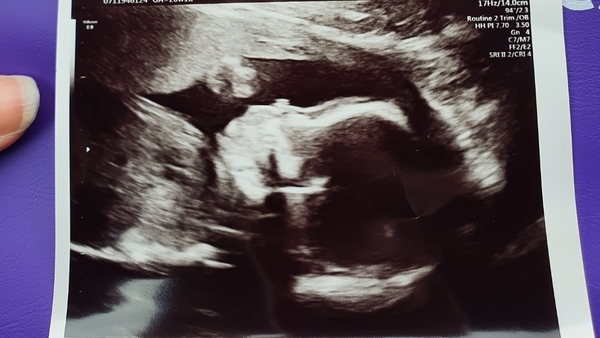

I had my 12 week scan today. All looked good. NT measurement was 2.2mm which they said was fine. I'm decided to get the harmony test done on Tuesday though. Just feel like I need to have it to feel relaxed (hopefully!).

Scan pic came out quite nice. I'm 12 weeks and 6 days today and have a due date of 10.10.20.

@Aria2015 glad all is well, lovely to see another new scan picture.